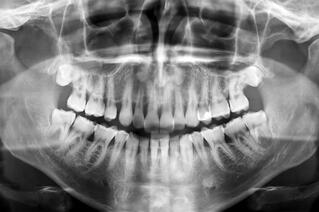

Orthognathic surgery, or corrective jaw surgery, is used to correct a bad bite, or malocclusion, that cannot be resolved through orthodontic care alone. Generally, such issues are related to problems with jaw formation and misalignment. Among the most common of these is severe underbite, which causes the lower jaw to protrude, giving it an elongated appearance. If you're suffering with this problem, you're sure to be curious about how your Singapore oral surgeon can help.

To properly align a protruding lower jaw, incisions will generally be made behind the third molars, allowing your surgeon to separate the front and rear portions of the jawbone. The rear portion is then modified to allow proper jaw positioning. Depending upon your particular circumstances, your repositioned jaw may be secured with surgical plates, screws or other devices to ensure proper healing, and further orthodontic work may be necessary after surgery to obtain optimal results.